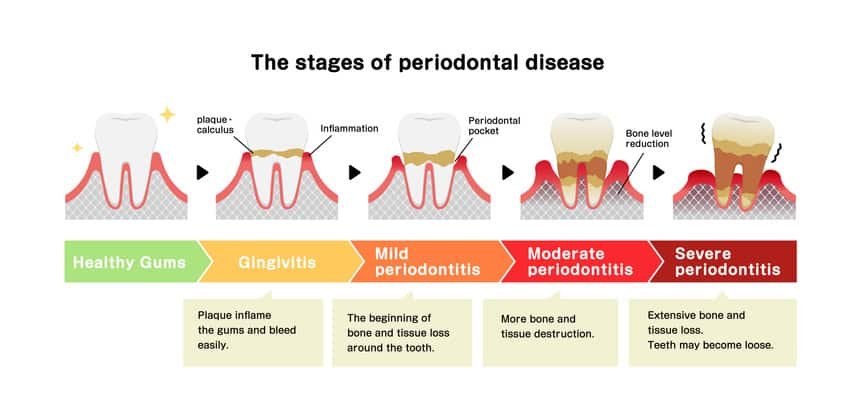

- Periodontitis (Advanced Gum Disease): This condition affects the underlying bone. If it progresses, teeth become loose and cause swelling. Unlike a cavity that usually affects one tooth, gum disease often impacts the whole mouth. We use 3D CBCT scans to evaluate every tooth. If the situation isn’t clear, we always attempt a “saving protocol” (such as deep cleaning) and monitor the results before moving toward an irreversible extraction.